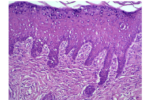

آلژیسایت پلاس یک پانسمان پوستی شفاف بر پایه دو پلیمر طبیعی و حاوی داروهای آنتی اکسیدان و آنتی باکتریال است که توسط شرکت پیشگامان ترمیم و شفای پارس بهصورت فیلم هیدروژلی تولید میگردد. این محصول بر پایه علوم مهندسی پزشکی، زیست مواد، مهندسی شیمی و مهندسی بافت طراحی و تولیدشده است. آلژیسایت پلاس در مواردی مانند سوختگی شدید، زخم دیابتی، زخم بستر، زخمهای عمیق پوستی و یا مواردی که زخمهای شدید پوستی جهت ترمیم به زخم پوش و یا پانسمان نیاز دارد مورداستفاده قرار میگیرد. مصرفکنندگان این پانسمان پوستی متخصصین پوست، جراحی زیبایی، بیمارستان سوانح سوختگی، بیمارستانهای دولتی و خصوصی، مراکز خصوصی درمان زخم، مراکز تحقیقاتی و افرادی که از انواع زخمهای مزمن پوستی رنج میبرند. این پانسمان نوین دارای قابلیت تنظیم فرمولاسیون، کنترل خواص فیزیکو شیمیایی، بارگذاری دارو و کنترل رهایش انواع مختلف دارو است.

- بهبود رشد و تکثیر سلولهای پوستی در محل آسیب

- افزایش ۲ برابری سنتز کلاژن در مقایسه با نمونههای تجاری مشابه

- افزایش میزان رگ زایی در محل آسیب

- تسریع ترمیم و بازسازی زخمهای عمیق و مزمن پوستی در آزمایش درونتن